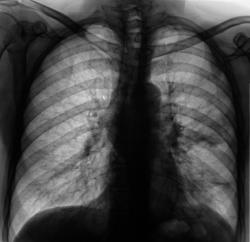

Флюорограмма.